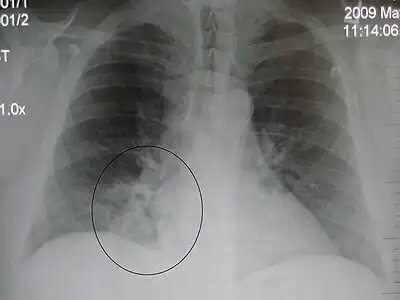

Occult pneumonia is a pneumonia that is not observable directly by the eye, but can only be shown indirectly, especially by radiography. Occult pneumonia can be made visible by chest X-rays.